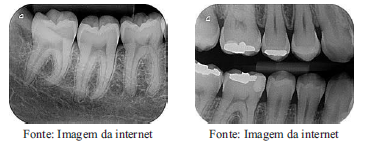

As imagens abaixo ilustram dois tipos de radiografias odontológicas. A denominação CORRETA dessas radiografia é, respectivamente: